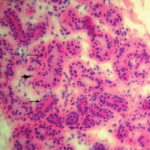

Eccrine unit situated in deep dermis = وحدةغدية ناتحة تتوضع في الادمة العميقة